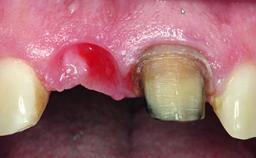

A healthy 23-year-old female patient was referred for a consultation on replacing tooth 21 with an implant-supported restoration. The patient had recently moved to the area and reported a history of endodontic and periodontal treatment for tooth 21. The tooth had been deemed non-restorable by her previous periodontist but since she was going to be moving, he recommended consulting to a dentist in her new city to continue her treatment. A review of her medical history yielded no significant findings and no known drug allergies. The analysis of her smile revealed a medium to high symmetrical smile line and a slightly discolored tooth 21.